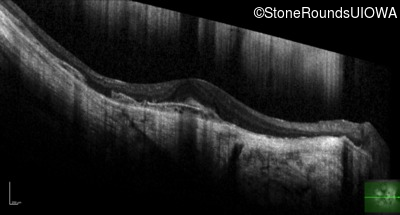

Optical Coherence Tomography - Left - 20/25 +2

Exemplar / OCT Stack